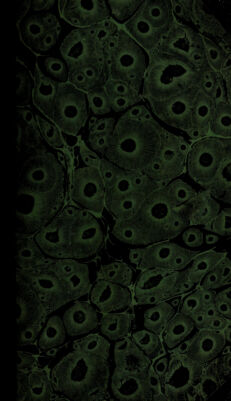

Dictionnaire de médecine-pratique et de chirurgie / [M.J.F. Alexandre Pougens].

- Pougens, M. J. F. Alexandre.

- 1820